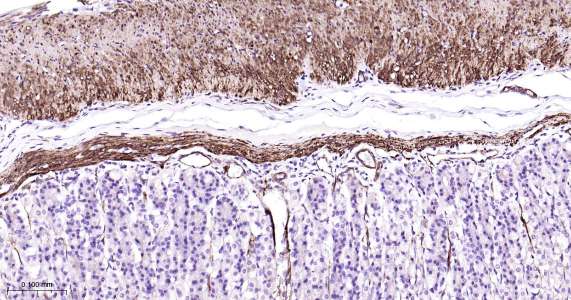

Immunohistochemical analysis of paraffin embedded mouse stomach tissue slide using IHC0473M (Mouse Vinculin IHC Kit).